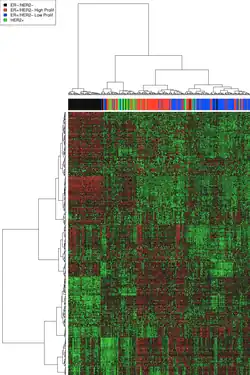

Molecular subtype

Receptor status was traditionally considered by reviewing each individual receptor (ER, PR, HER2) in turn, but newer approaches look at these together, along with the tumor grade, to categorize breast cancer into several conceptual molecular classes[46] that have different prognoses[39] and may have different responses to specific therapies.[47] DNA microarrays have assisted this approach, as discussed in the following section. Proposed molecular subtypes include:

- Basal-like: ER-, PR- and HER2-; also called triple negative breast cancer (TNBC).[48] Most BRCA1 breast cancers are basal-like TNBC.

- Luminal A: ER+ and low grade

- Luminal B: ER+ but often high grade

- Luminal ER-/AR+: (overlapping with apocrine and so called molecular apocrine) - recently identified androgen responsive subtype which may respond to antihormonal treatment with bicalutamide[44]

- ERBB2/HER2-amplified: has overexpressed HER2/neu[40]

- Normal breast-like[39][46][49]

- Claudin-low: a more recently described class; often triple-negative, but distinct in that there is low expression of cell-cell junction proteins[48] including E-cadherin[48] and frequently there is infiltration with lymphocytes.[46][50][51]

DNA classification

DNA microarrays

Background

DNA microarrays have compared normal cells to breast cancer cells and found differences in the expression of hundreds of genes. Although the significance of many of those genetic differences is unknown, independent analyses by different research groups has found that certain groups of genes have a tendency to co-express. These co-expressing clusters have included hormone receptor-related genes, HER2-related genes, a group of basal-like genes, and proliferation genes. As might therefore be anticipated, there is considerable similarity between the receptor and microarray classifications, but assignment of individual tumors is by no means identical. By way of illustration, some analyses have suggested that approximately 75% of receptor classified triple-negative breast cancers (TNBC) basal-like tumors have the expected DNA expression profile, and a similar 75% of tumors with a typical basal-like DNA expression profile are receptor TNBC as well. To say this in a different way to emphasize things, this means that 25% of triple-negative breast cancer (TNBC) basal-like tumors as defined by one or other classification are excluded from the alternative classification's results. Which classification scheme (receptor IHC or DNA expression profile) more reliably assorts particular cancers to effective therapies is under investigation.